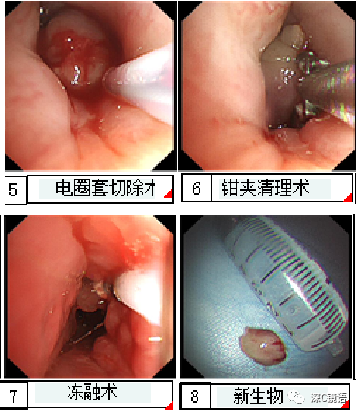

医疗方面:目前,我科室能开展呼吸内镜相关诊断与治疗技术,具体如下:诊断技术包括经支气管镜冲洗术、灌洗术、刷检术、活检术、针吸活检术、环形超声以及内科胸腔镜等;治疗技术包括球囊扩张术、支架植入术、高频电凝术、高频电圈套治疗、激光治疗、冷冻治疗、局部注药治疗等。秉承“患者所需,医者所为”的宗旨,为肺部感染、肿瘤、气道异物、不明原因胸腔积液,尤其是气道结核的患者,提供综合诊治方案。